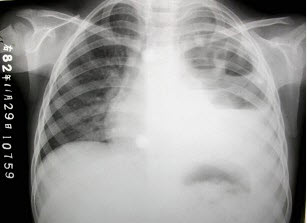

女,8岁,寒战、高热一周,如图所示,最可能的诊断为()

A . 左侧肺不张

B . 左侧胸腔积液

C . 左侧多发性肺脓肿

D . 左心室增大

E . 以上都不正确